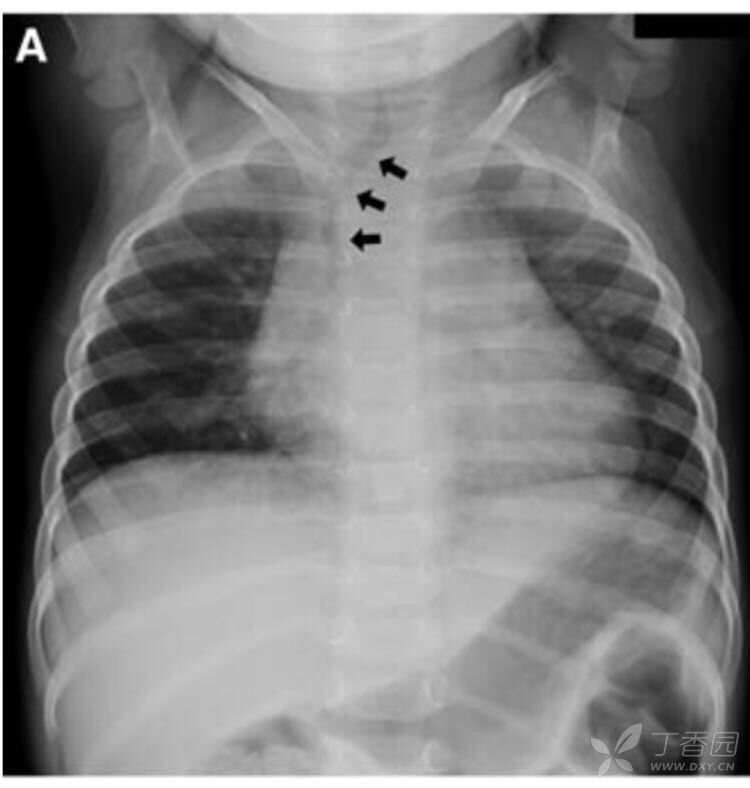

胸片显示气管向右弯曲(图a,箭头所示)。

因怀疑胸腔内肿物而进行胸部CT检查,显示气管有右偏(图,B,箭头所示),但没有发现肿物或血管压迫。患儿在影像检查时哭吵。